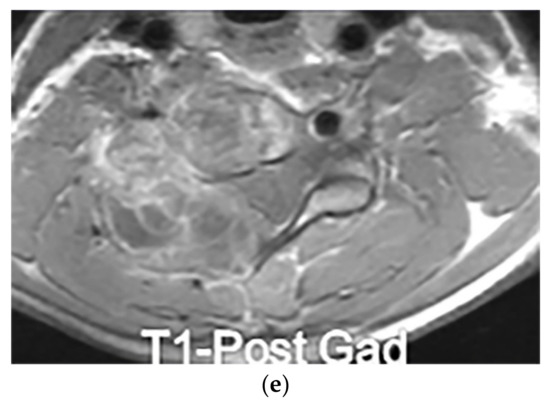

Neuroblastoma appears as an ill-defined paravertebral soft tissue mass on a CT scan with heterogeneous attenuation caused by hemorrhage, necrosis, or cystic degeneration. Internal calcification is seen at least in 30% of cases [7,16]. MRI shows irregular margin with possible local invasion to the spinal canal, presenting T1-hypointensity and T2-hyperintensity with heterogeneous enhancement. Calcification has a signal void in all sequences (Figure 18 and Figure 19). It is reported that tumors with higher metabolic activity on 18F-FDG PET/CT have lower overall survival [44,45]. Metaiodobenzylguanidine labeled as 123I (MIBG) is highly sensitive for detecting catecholamine-producing tumors like neuroblastoma [7,16].

Figure 18.

A 6-year-old boy with posterior mediastinal mass with histopathological confirmation for Neuroblastoma. Axial (a) T2W shows an ill-defined lobulated group (arrow) with heterogeneous and hyper-intense signal intensity and area of a signal void within the posterior mediastinum. It has intracanal extension via right-sided neural foramina and extradural components at multiple levels. It displaced the spinal cord anteriorly, as shown in sagittal T1W after gadolinium administration (arrow) (b).

Figure 19.

A 4-year-old girl with the opsomyoclonus-myoclonus syndrome. Sagittal (a) and axial (b) T2W images show large lobulated paraspinal masses (arrowhead) crossing the midline within the posterior superior mediastinum. It shows heterogeneous and hyperintense signal intensity with internal foci of the signal void caused by calcification. It extends through the spinal canal via neural foramina (arrow). Right anterolateral displacement of mediastinal great vessels is also identified.